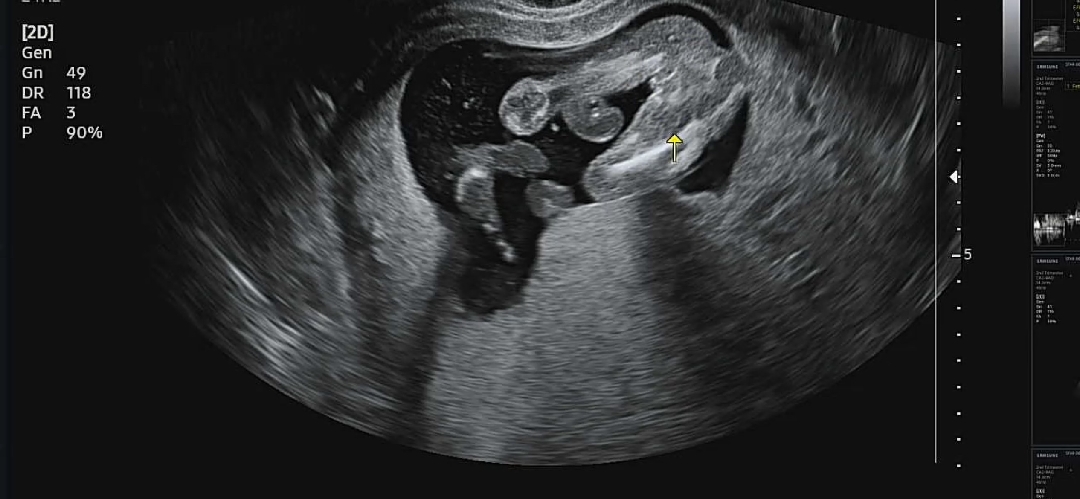

17주차 성별 봐주실 수 있나요?

아무리 봐도 딸 같은데..다른 분들 의견이 너무 궁금하네요!

아들요!

아들갔아요!! 저 오늘 병원갔는데 저희 애기 초음파 사진이랑 똑같아요! 가랑이 사이에 보이는게...